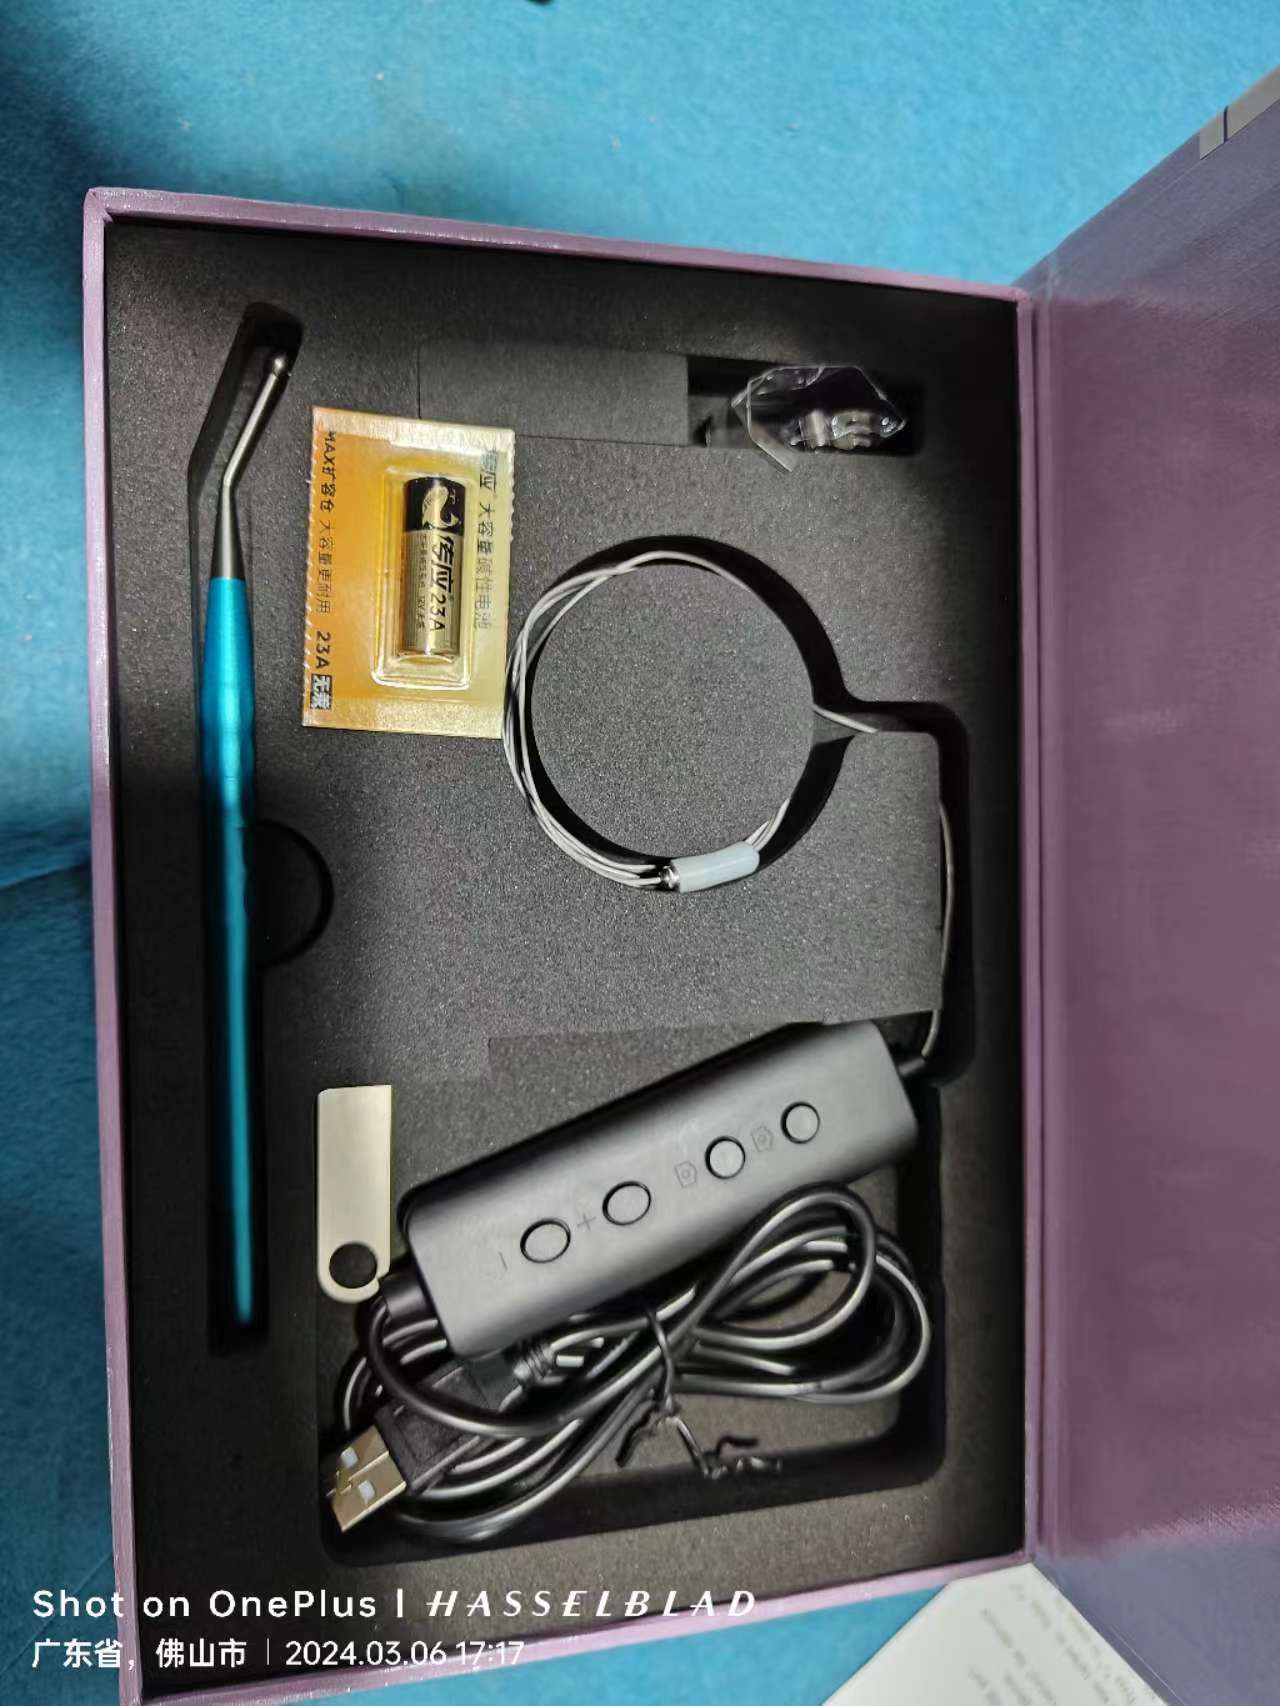

* With WIFI Padel to take image, higher efficient to work, more convenient

* Comes with system

* USB output